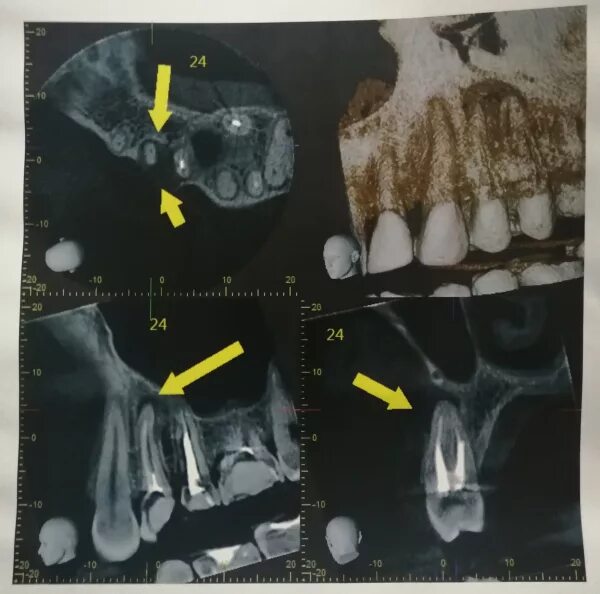

Киста зуба что это